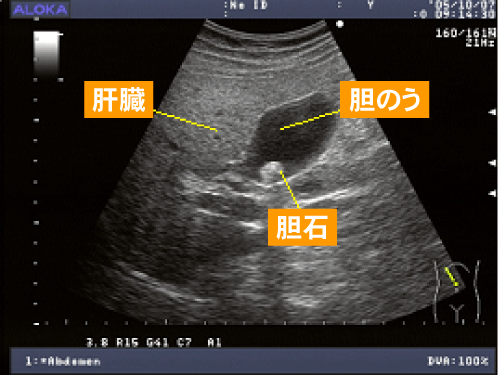

超音波検査で一番発見されることが多いのが、胆石(画像)です。他に胆のうポリープ、胆のうがんの診断にも有用です。